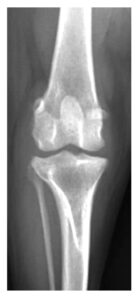

症例1. TPLOを実施した症例(7歳、ビーグル、9 kg)

| 治療前(側方像) | 治療後(側方像) | 治療前(前後像) | 治療後(前後像) |